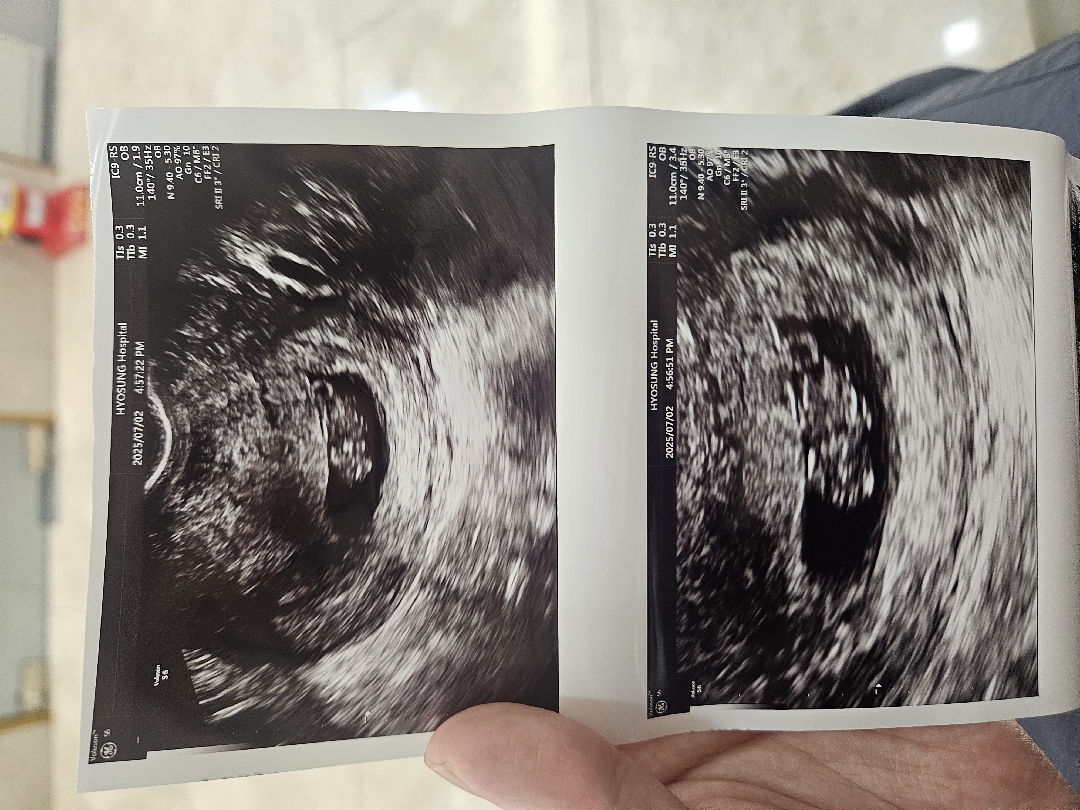

9주차 젤리곰 시기에 초음파를 찍었는데 이렇게 나왔네유ㅠ 젤리곰이 잘안보여서 조금 속상해욤.. 다른분들은 혹시 이렇게 보이면 따로 다시 찍으러 가시거나 그러셨나욤??